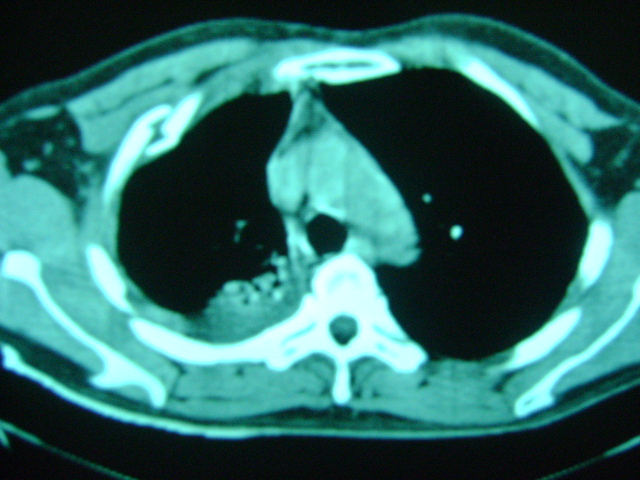

标题: CT16197:新手求教,M,42y,外伤入院,略感气紧,余无不适 [打印本页]

标题: CT16197:新手求教,M,42y,外伤入院,略感气紧,余无不适

肋骨骨折,肺挫伤,胸腔积液,不张?

肋骨骨折,右肺挫裂伤,右侧胸腔积液,没有气胸很奇怪啊

肋骨骨折,肺挫伤,胸腔积液,左肺代偿性气肿.

肋骨骨折,肺挫伤,胸腔积血.

右侧肋骨骨折,右肺挫伤,右侧胸腔积液(血)。

肋骨骨折,肺挫伤,双侧胸腔积血.

右上肺后段片状实变影有点状钙化,左下肺亦可见结节影,应考虑结核

肋骨骨折,肺挫伤,胸腔积液。